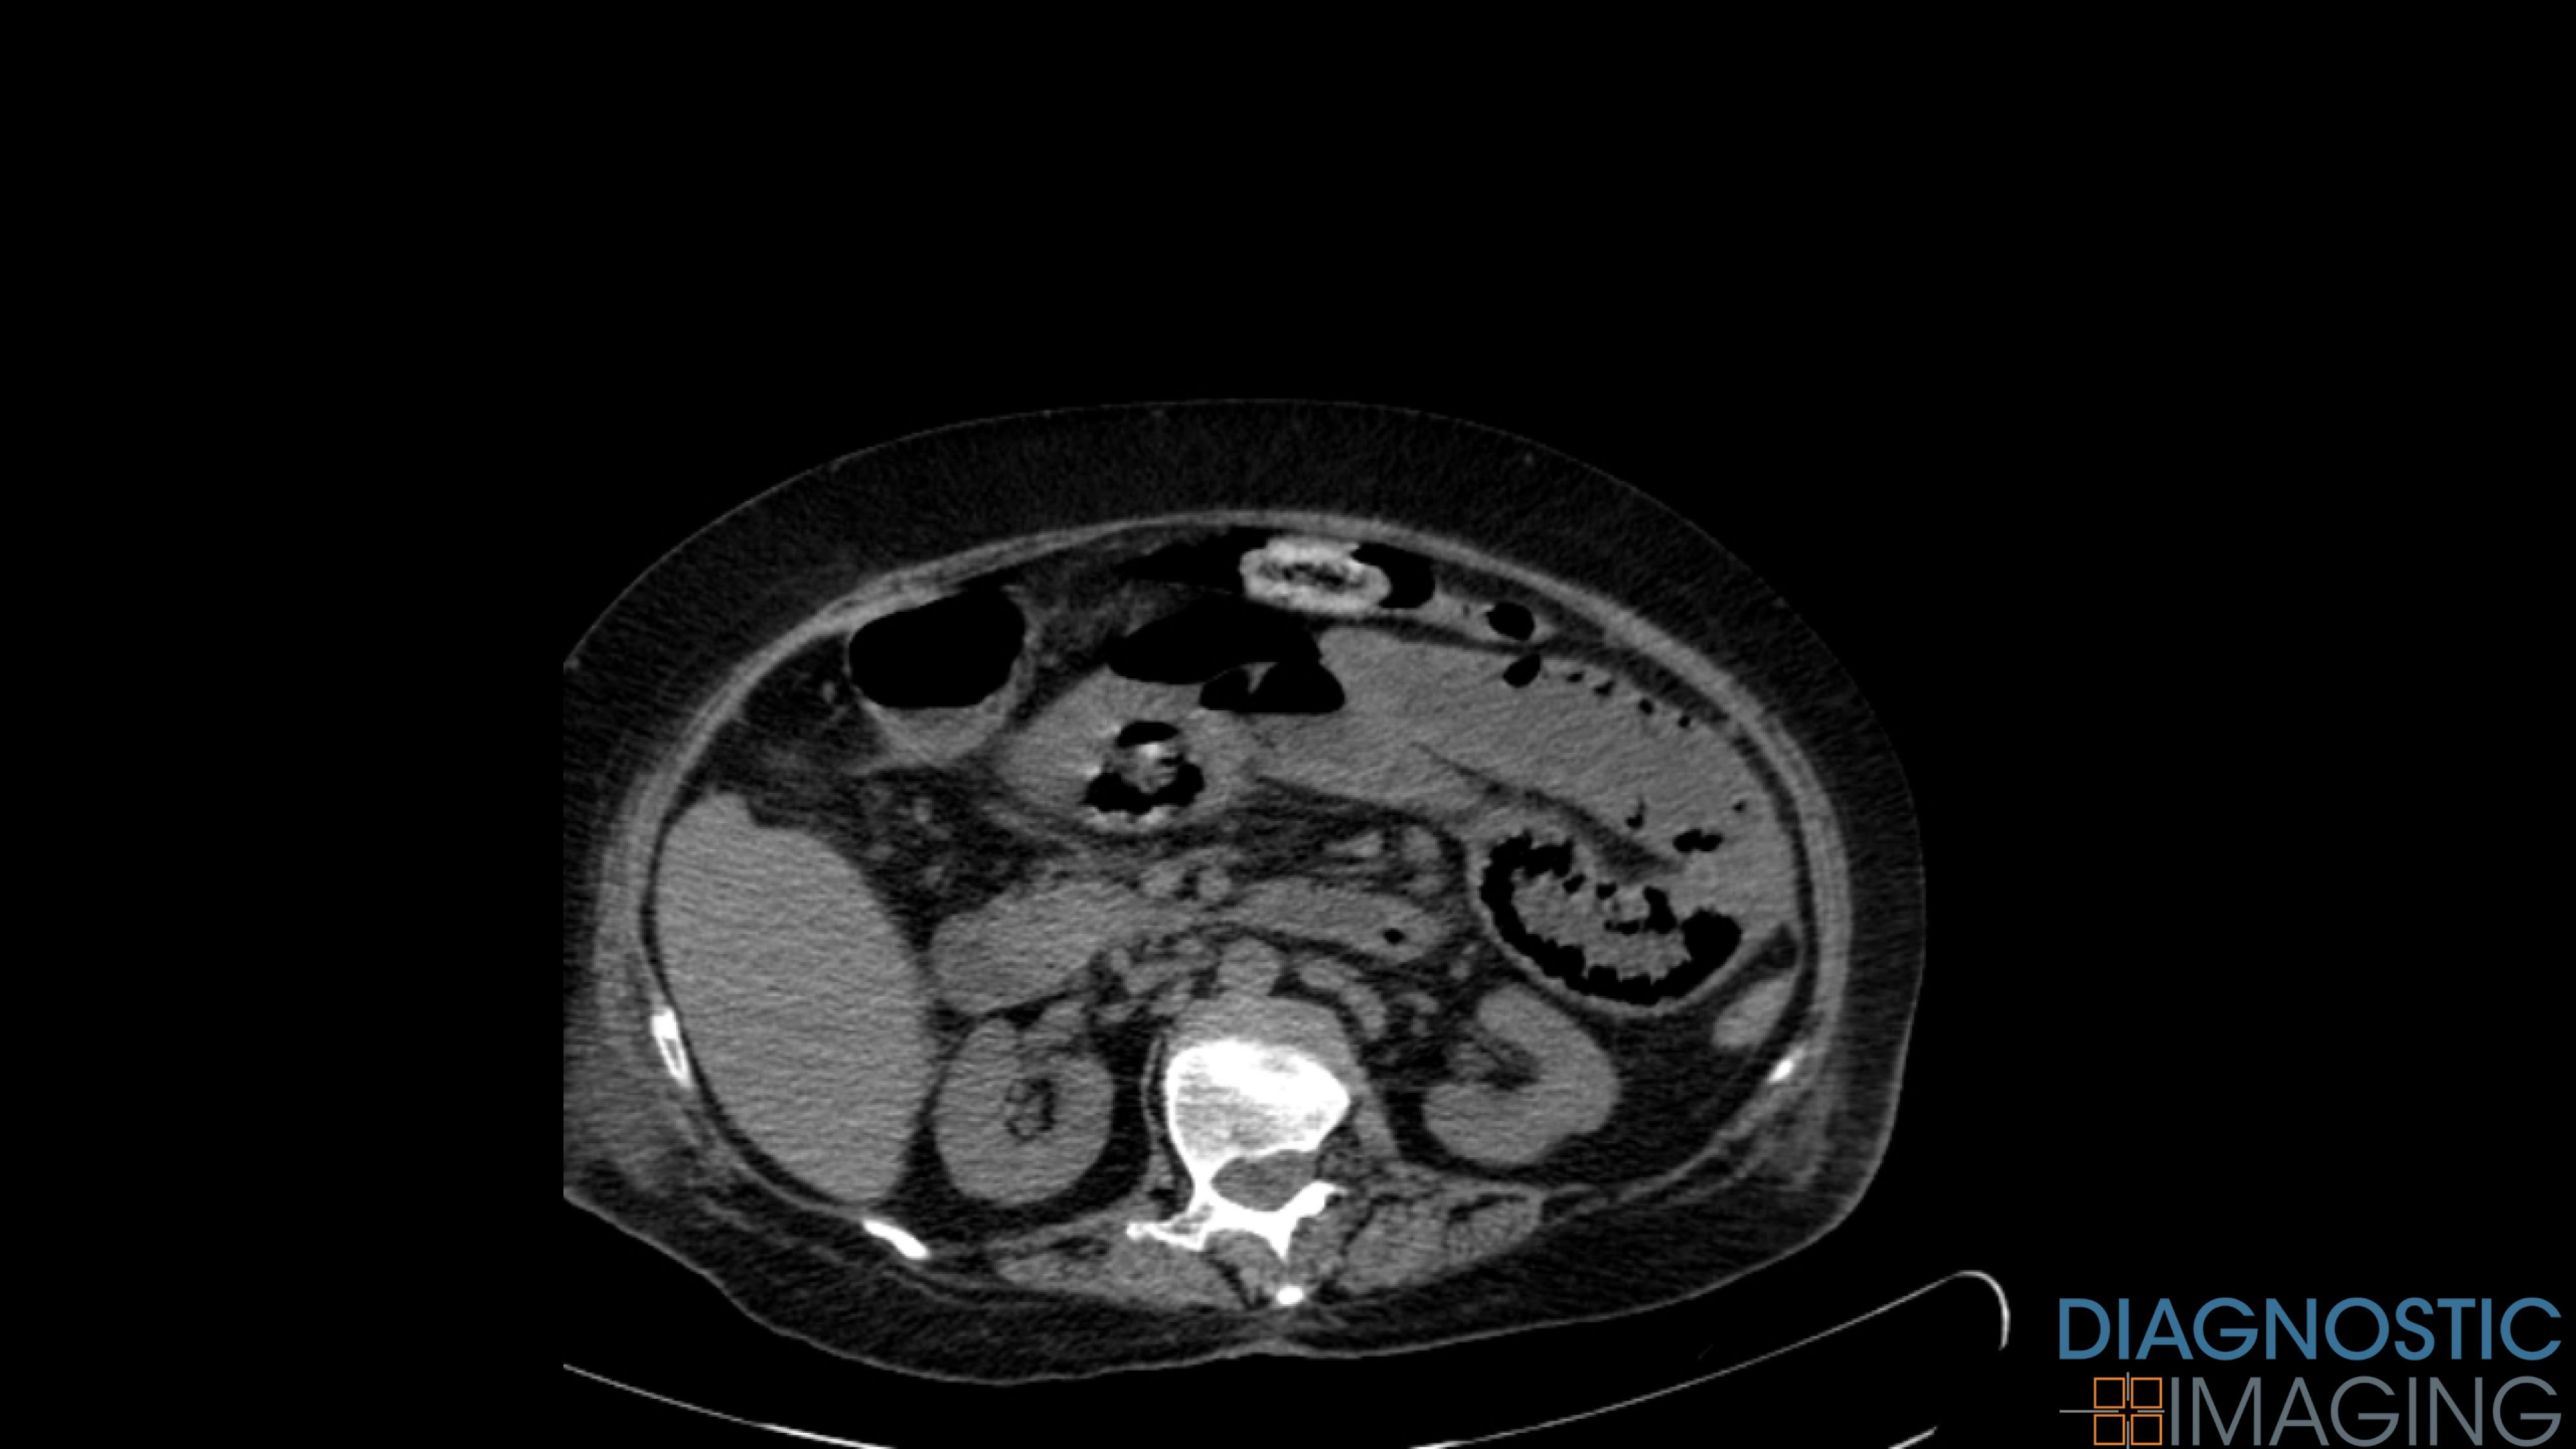

Case History: 60-year-old patient with vomiting and abdominal pain.